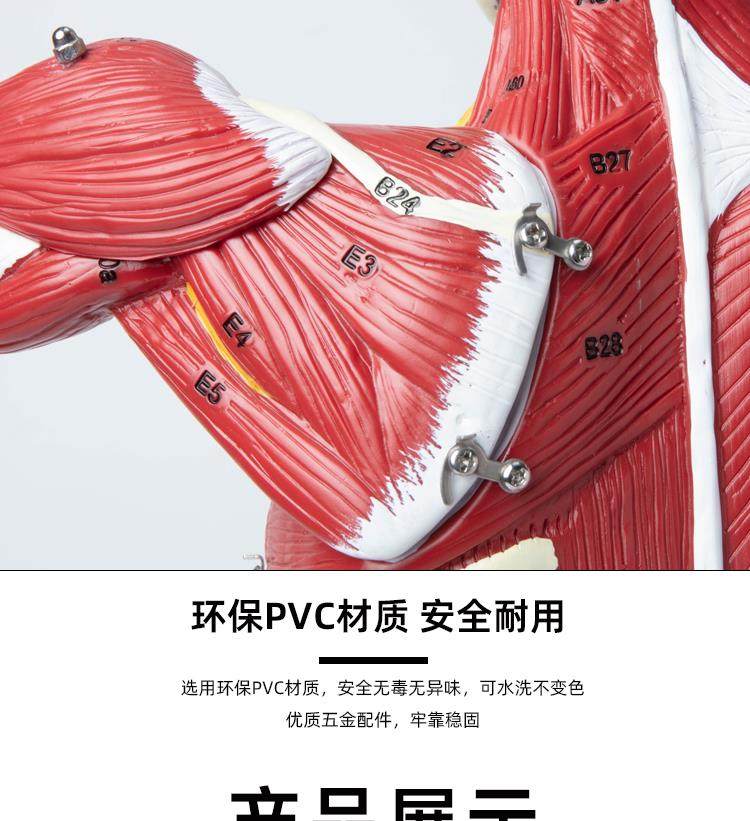

Human Body Muscle Internal Organ Disassembly Anatomy Structure Model Tissue Exercise Artificial Medical Teaching Aids

| Product Specifications | |

| Brand | No Brand (No Registered Trademark) |

| Model | 6622 |

| Color Classification | 85 Human Muscle Internal Organs Removable Organ,50cm Muscle Model |